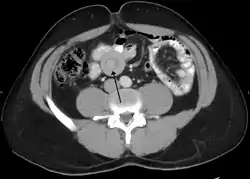

![]() انغماد معوي كما يظهر في التصوير المقطعي المحوسب انغماد معوي كما يظهر في التصوير المقطعي المحوسب | |